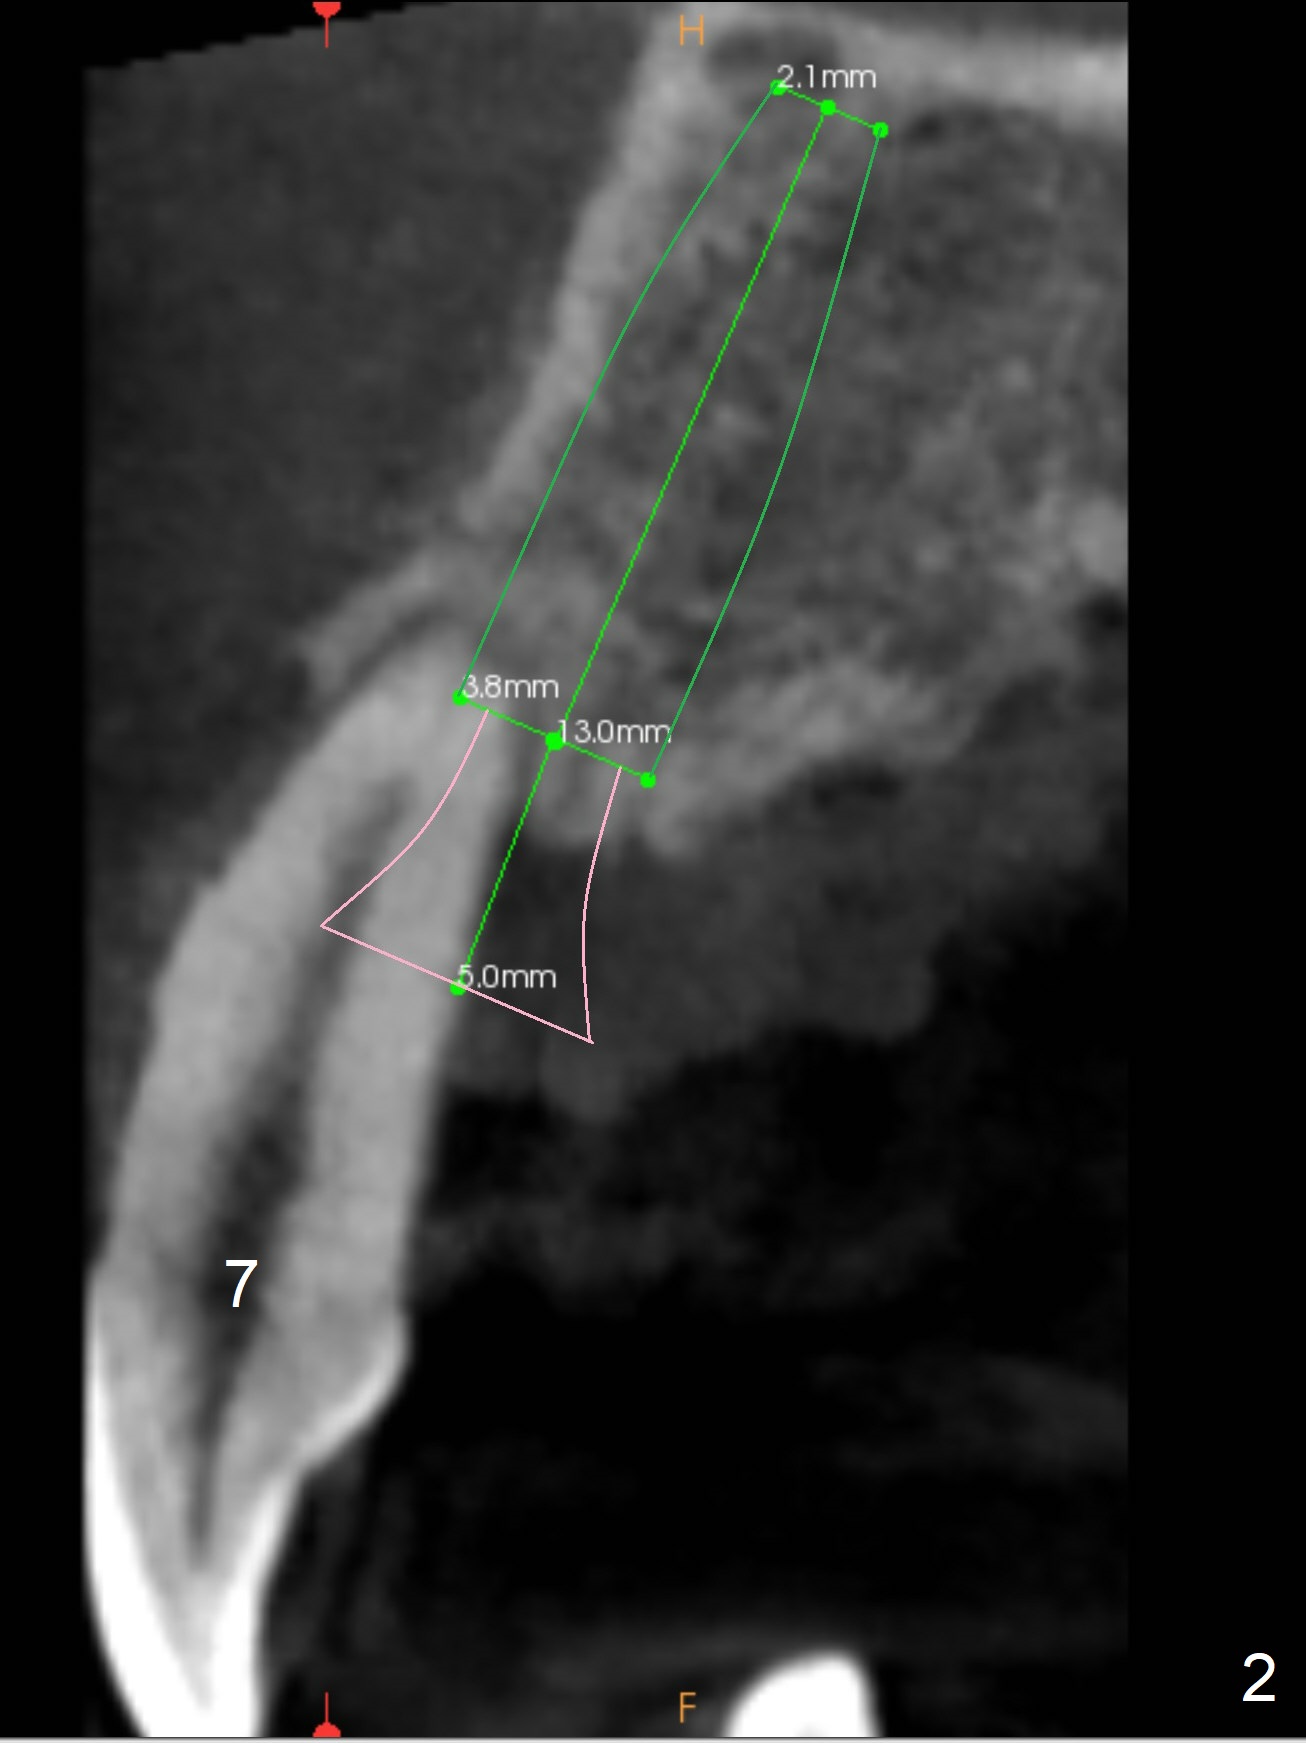

A 36-year-old man develops periodontal abscess around #7 post SRP for the lower quadrants. Last Saturday the pockets were irrigated with Hydrogen Peroxide. Metronidazole was prescribed. According to CT study on the teeth #6-10 (Fig.1-5), it appears that the tooth #7 is the most severely affected and therefore the most likely to be extraction for implant.